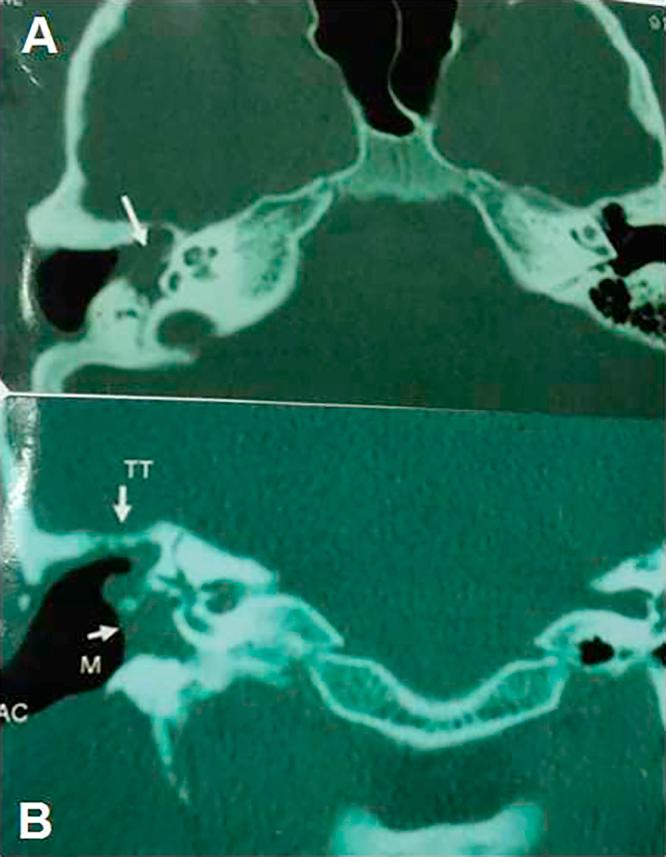

CT showed partial opacification of the tympanomastoid cavity in 10 ears and complete opacification in 21 ears. CT detects 10 cases out of 20 cases of recurrent cholesteatoma with sensitivity 47.6%, specificity 100%, and NPP 47.6%. DWI depicted 21 out of 20 cases proved cholesteatoma patients (sensitivity 100%, specificity 90%, PPV 95.2% and P value is 0.001). All MRI of patients without cholesteatoma were correctly interpreted as showing negative findings for cholesteatoma (specificity = 100%). The ADC of cholesteatoma group (21 ears) were ranged from 553 to 759 × 10 mm/s and the ADCs of non cholesteatoma group (10 ears) was ranged from 1495.8 to 1766.8 × 10 mm/s. Cut off value of cholesteatoma is ≤759 × 10 mm/s.

CT显示鼓室乳突腔部分混浊10耳,完全混浊21耳。CT在20例复发性胆脂瘤中检测出10例,敏感性为47.6%,特异性为100%,阴性预测值为47.6%。DWI在20例经证实的胆脂瘤患者中显示出21例(敏感性100%,特异性90%,阳性预测值95.2%,P值为0.001)。所有无胆脂瘤患者的MRI均被正确解读为胆脂瘤阴性结果(特异性 = 100%)。胆脂瘤组(21耳)的ADC值范围为553至759×10⁻⁶mm²/s,非胆脂瘤组(10耳)的ADC值范围为1495.8至1766.8×10⁻⁶mm²/s。胆脂瘤的截断值为≤759×10⁻⁶mm²/s。